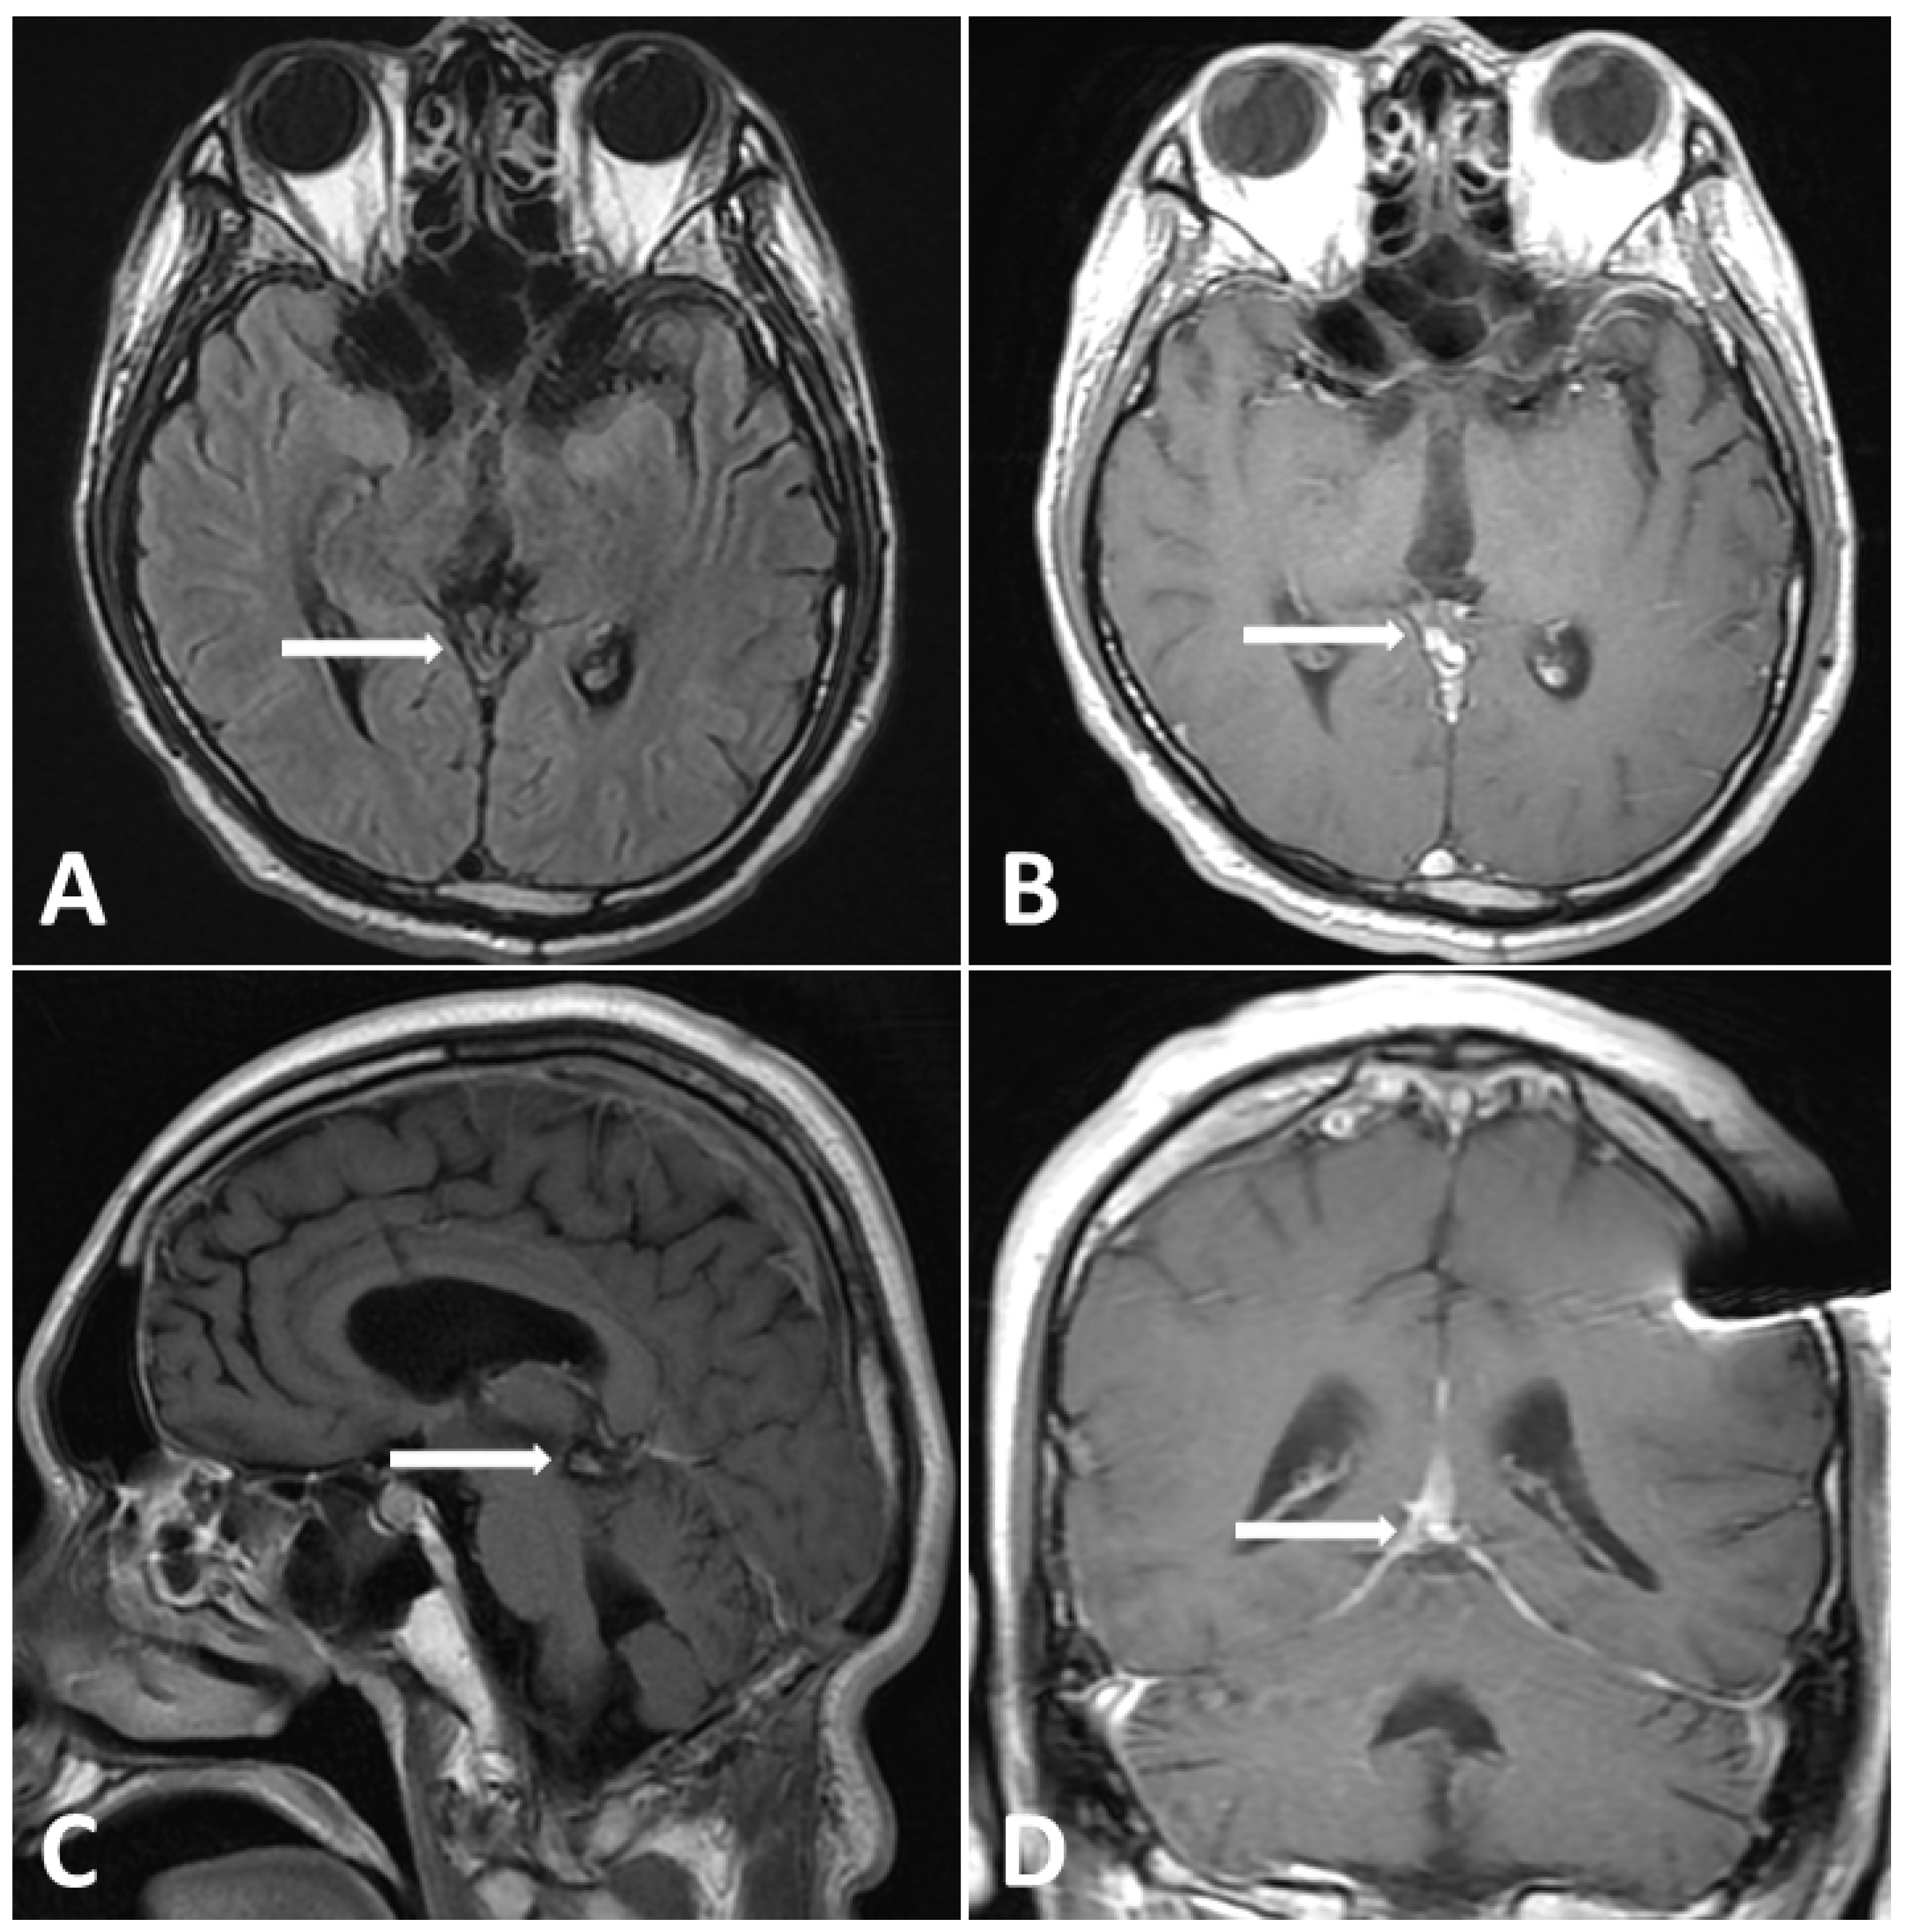

Figure 5.

Follow-up MRI (3 months post treatment). (A) T2-FLAIR images showing evidence shrinkage of lesion without perifocal edema. (B–D) Gadolinium-enhanced MRI, revealing dramatic shrinkage of previous pineal tumor.